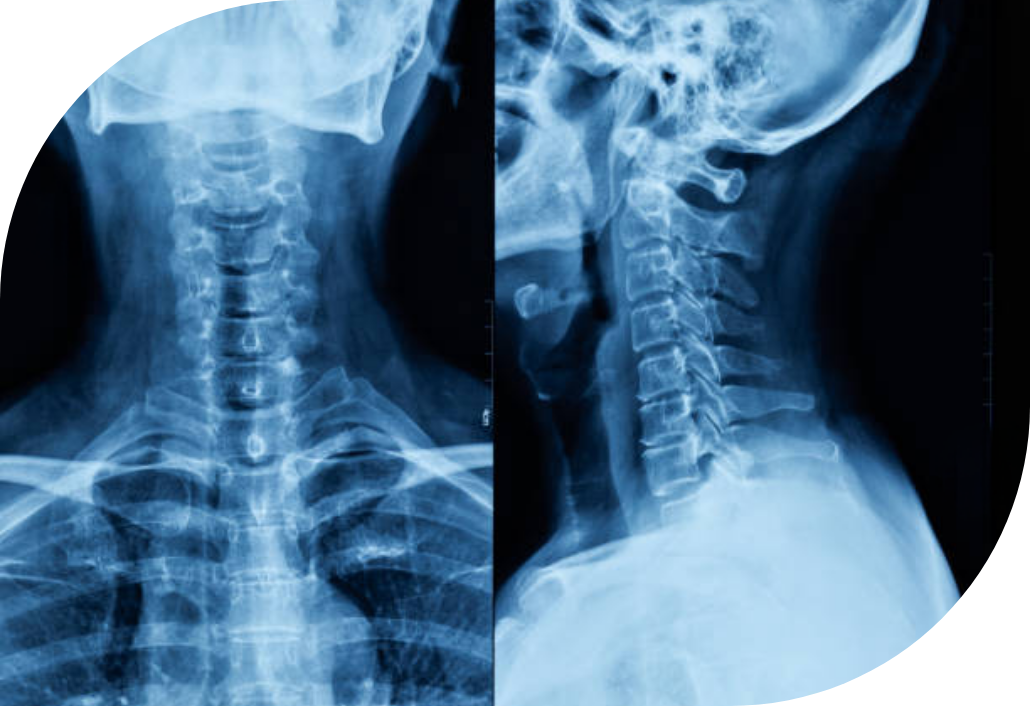

Las radiografías son una de la herramientas mas importantes en las evaluaciones iniciales y de progreso. Éstas nos permiten observar el estado estructural de la espina dorsal, su alineamiento y condiciones que pueden estar presentes en la columna y sus tejidos adyacentes.